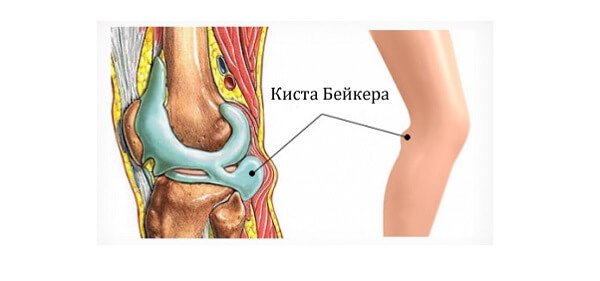

Фото и диагностика кисты Бейкера